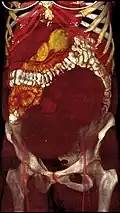

A very large (9 cm) fibroid of the uterus which is causing pelvic congestion syndrome as seen on CT -